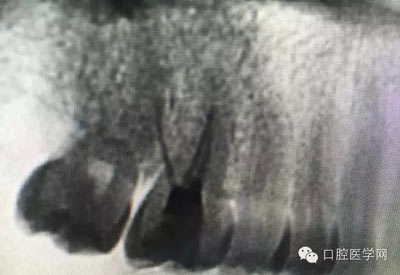

這是一例外院樹脂修復后十個月出現(xiàn)牙髓炎癥狀的患者。遇到這樣子的患者大家會怎么做,證明選擇,還有就是可做可不做治療的如何去平衡。

根管治療,我們在大學的時候就學習的東西,標準就在那里放著,可是很多時候我們熟視無睹,放任我們的想象去做。我們多些重視,多些心思,會好很多,認真對待每顆牙齒。